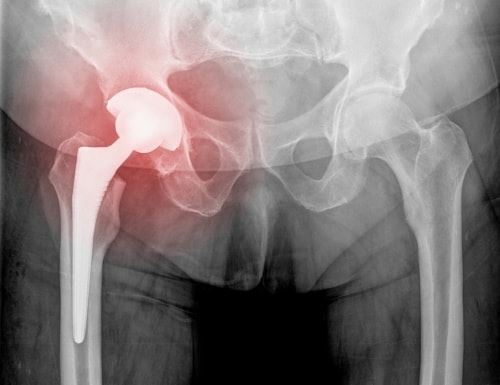

This is what happened with the Stryker Rejuvenate and ABG II hip implants, which, after less than two years on the market, were found to fret and corrode at the modular-neck junction. For comparison, a typical hip replacement lasts 15 to 20 years. The defects in the Stryker implants may cause adverse local tissue reactions, hip failure, necrosis, metallosis, and the need for revision surgery. Other metal-on-metal hip implants have faced similar issues, with DePuy recently settling a class-action lawsuit with about 8,000 patients.